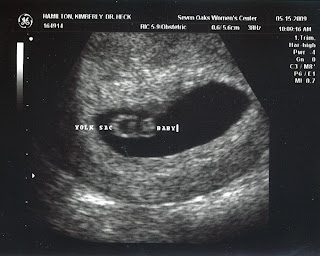

Weston and I just got back from our doctor's appointment and ultrasound and now know that we are having a precious BABY GIRL! In highschool and college, Weston nicknamed me, "Baby Girl", would always call me that, cathing flack from his friends. Now, he will have, his own real Baby Girl!! The ultrasound went so well and was so much fun. The technician said that everything looked normal and that nothing she saw concerned her, so what wonderful blessings we have had today!! When Weston and I walked out of the ultrasound room, we had another blessing waiting for us. Our dear friend Courtney and her two boys, McCoy and Hudson, were waiting there with a boy and girl gift in hand to surprise us! It was so great to share the news and to graciously receive our baby girl's first little gift, a hunting cap, camo equipped and all, with a touch of pink and the word's "Future Hunting Princess"! How adorable!! We can't wait to get started on picking out the perfect name for our princess and decorating her nursery! Thank you all for your prayers over our little angel!!! Oh how wer are blessed! I will post pictures of Baby Hamilton this weekend!

Well, after almost 3 years of marriage, raising from birth two adorable puppies, Gus and Bella, building a home in the hill country, and starting and maintaining some what exciting careers, we decided to make life a little more exciting, a little more crazy, and a little more FUN by adding a baby to the mix. Weston and I are going to be parents and we couldn't be more thrilled! We have seen the flutter of the heart beat in a sonogram, seen our beautiful baby (girl or boy???) and discovered what a yoke sack is, which sounds pretty gross but is pretty vital! We love our doctor who we never would have found if it wasn't for some pretty amazing "mommy" role models in my life...you know who you are! We are pretty confident in our ability to raise a child as we have had over 4 years experience in caring for Gus and Bella, who in their own right, claim to be humans....who are we to shatter their dreams! All in all, I am feeling pretty great, except for the small disappointment that my clothes seem to be shrinking....oh well, just another excuse to hit the shops! I would love any cool - trendy - not too over the top price wise, shopping tips for maternity clothes if any are out there. My due date is December 31st so we are planning on ringing in the new year like never before!!

some what exciting careers, we decided to make life a little more exciting, a little more crazy, and a little more FUN by adding a baby to the mix. Weston and I are going to be parents and we couldn't be more thrilled! We have seen the flutter of the heart beat in a sonogram, seen our beautiful baby (girl or boy???) and discovered what a yoke sack is, which sounds pretty gross but is pretty vital! We love our doctor who we never would have found if it wasn't for some pretty amazing "mommy" role models in my life...you know who you are! We are pretty confident in our ability to raise a child as we have had over 4 years experience in caring for Gus and Bella, who in their own right, claim to be humans....who are we to shatter their dreams! All in all, I am feeling pretty great, except for the small disappointment that my clothes seem to be shrinking....oh well, just another excuse to hit the shops! I would love any cool - trendy - not too over the top price wise, shopping tips for maternity clothes if any are out there. My due date is December 31st so we are planning on ringing in the new year like never before!!

some what exciting careers, we decided to make life a little more exciting, a little more crazy, and a little more FUN by adding a baby to the mix. Weston and I are going to be parents and we couldn't be more thrilled! We have seen the flutter of the heart beat in a sonogram, seen our beautiful baby (girl or boy???) and discovered what a yoke sack is, which sounds pretty gross but is pretty vital! We love our doctor who we never would have found if it wasn't for some pretty amazing "mommy" role models in my life...you know who you are! We are pretty confident in our ability to raise a child as we have had over 4 years experience in caring for Gus and Bella, who in their own right, claim to be humans....who are we to shatter their dreams! All in all, I am feeling pretty great, except for the small disappointment that my clothes seem to be shrinking....oh well, just another excuse to hit the shops! I would love any cool - trendy - not too over the top price wise, shopping tips for maternity clothes if any are out there. My due date is December 31st so we are planning on ringing in the new year like never before!!

some what exciting careers, we decided to make life a little more exciting, a little more crazy, and a little more FUN by adding a baby to the mix. Weston and I are going to be parents and we couldn't be more thrilled! We have seen the flutter of the heart beat in a sonogram, seen our beautiful baby (girl or boy???) and discovered what a yoke sack is, which sounds pretty gross but is pretty vital! We love our doctor who we never would have found if it wasn't for some pretty amazing "mommy" role models in my life...you know who you are! We are pretty confident in our ability to raise a child as we have had over 4 years experience in caring for Gus and Bella, who in their own right, claim to be humans....who are we to shatter their dreams! All in all, I am feeling pretty great, except for the small disappointment that my clothes seem to be shrinking....oh well, just another excuse to hit the shops! I would love any cool - trendy - not too over the top price wise, shopping tips for maternity clothes if any are out there. My due date is December 31st so we are planning on ringing in the new year like never before!!